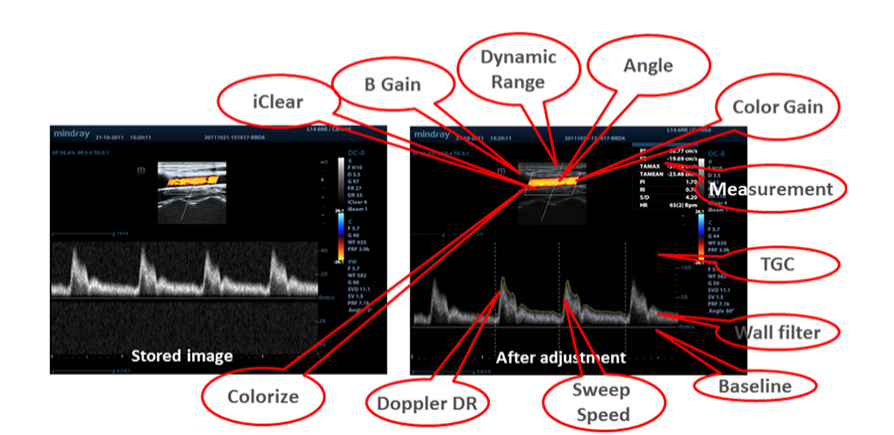

Raw Data

Optimale flexibiliteit voor nabewerking van de opgeslagen beelden, inclusief parameteraanpassingen, het toevoegen van opmerkingen en metingen, voor een optimale productiviteit tijdens het scannen